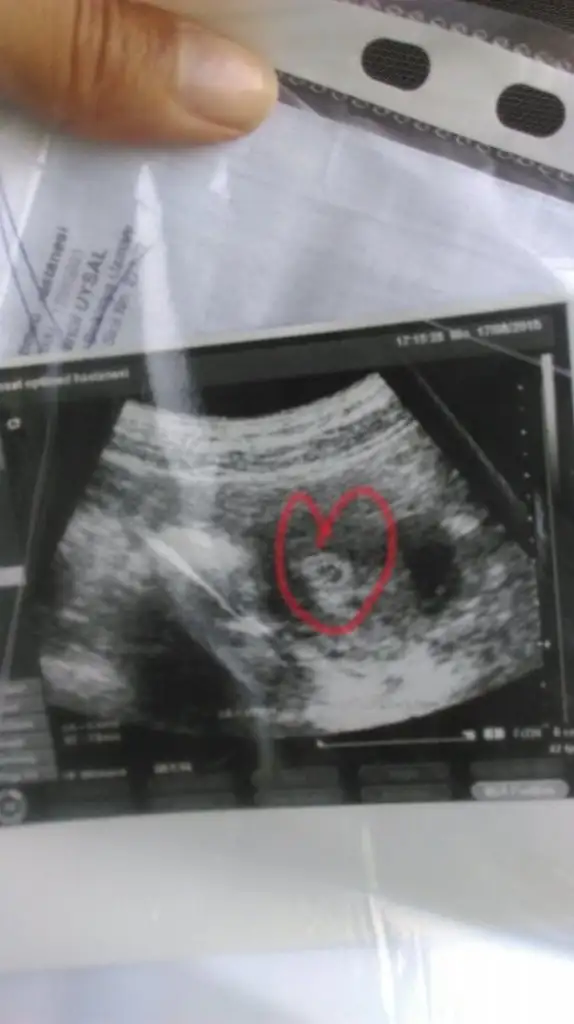

Gozun aydin amin hepimiz saglikla kucaklarimiza alalimmrhaba beni hatrlayan varmi bilmiyorum dun dr gttm kesemizi gordum cok guzel bi duygu yarabbim simdi dusunuyorumda bugune kadar uzuldugum sevindigim agladigim guldugum hersey nekadar bosmus asil huzur buymus cok sukur rabbim banada nasip etti dilerimki isteyen herkes tatsin bu duyguyu